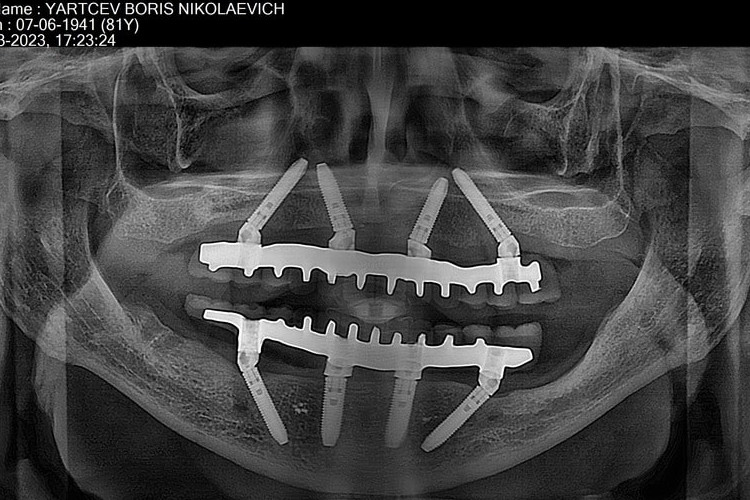

All-on-4 на рентгеновских снимках

![]() |